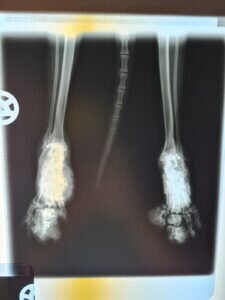

Viele Scottish Fold leiden ihr gesamtes Leben lang unter schmerzhaften degenerativen Gelenkerkrankungen. Die Mutation der Knorpel, die die Knickohren verursacht, verursacht auch die Mutation der Knorpel im Bewegungsapparat. Die Gelenke versteifen, die Knochen verwachsen und jede Bewegung wird mit der Zeit immer beschwerlicher und schmerzhafter.

Wir ließen sie röntgen, wussten aber im Grunde schon, was uns erwarten würde.